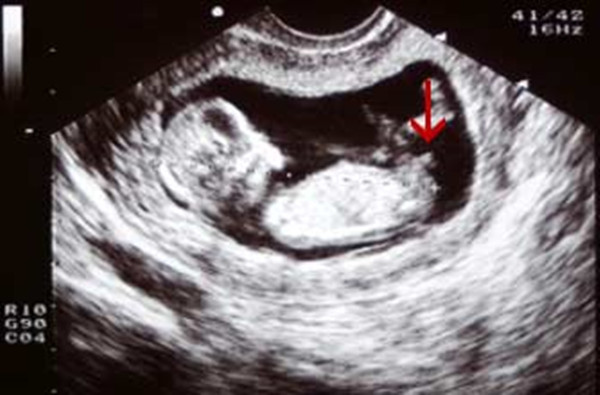

第一点:看胎儿尾椎骨末端和小腹之间的突出点 , 即生殖器位置

NT检查时 , 男宝宝和女宝宝的生殖器形状是不一样的 。 女孩 , 生殖器是没有向外突出 , 没有向上的角度 , 看上去比较平 , 与躯体的角度一般不会超过30度;男孩 , 生殖器是直接向外突出, 身体与特征点之间有角度 , 一般角度会大于30度 。